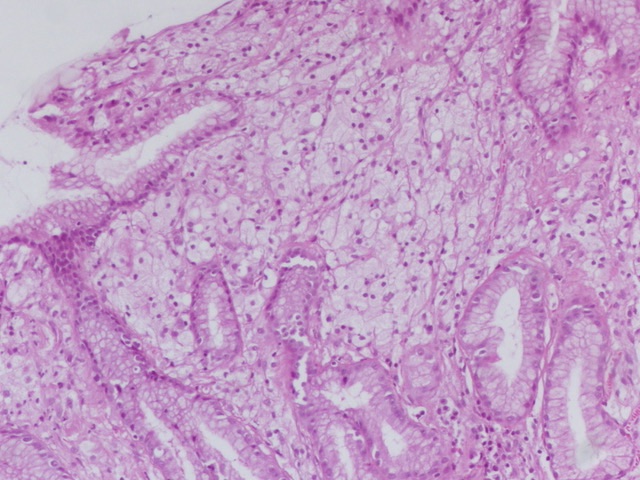

How not to share this #beautyinB9 #GIPath #Pathresidents #PathOutPic Gastric xanthomas appear as pale or yellowish plaques or nodules, typically less than 3 mm in size, located in the gastric mucosa. They are often found in clusters, more frequently along the lesser curvature

2

12

43